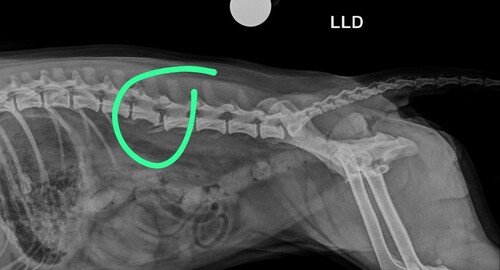

A Babalu sofreu uma lesão na coluna e na pelve e está sem movimentos nas patinhas inferiores, por isso ela fez uma uma operação de emergência e vai precisar também de cuidados pós operatórios como remédios e cuidados especiais. Além dessa cirurgia o médico identificou que ela está com uma lesão no ligamento de um dos joelhos e depois vai precisar de mais uma operação. Vamos ajudar a Babalu e trazer a alegria dela de volta? ❤️